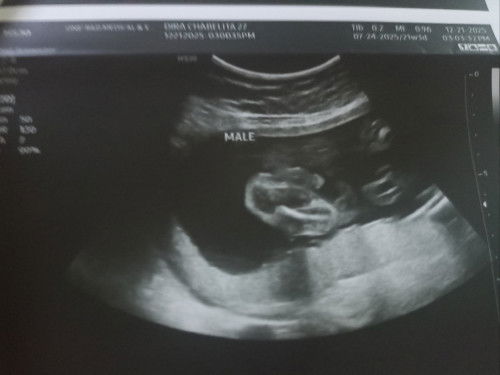

First time expecting po, 8 weeks na po ako now. Nakapagpa-TVS na twice, una: 5weeks pa lang wala pa heartbeat, tapos at 7weeks may confirmation na ng embryo at heartbeat. Ang next prenatal ko kasi sa week 11 ko tapos wala naman nabanggit si doc na Ultrasound pero syempre excited ako makita si baby na gumagalaw kaya gusto ko sana week 12 magpa-ultrasound kasi transition na for 2nd trimsester nito pero sabi 14weeks daw ang gender reveal. Ayaw ko naman i-expose sa madaming ultrasound si baby so ANO KAYA BEST WEEK PARA MAGPA-ULTRASOUND SA 2ND TRIMESTER? After ng 11weeks na pre-natal ko, week15 pa kasi yung sunod na check-up. TYSM IN ADVANCED PO SA MAY MGA EXPERIENCE NA #Needadvice #firsttimemom #pregnancy #askmommies